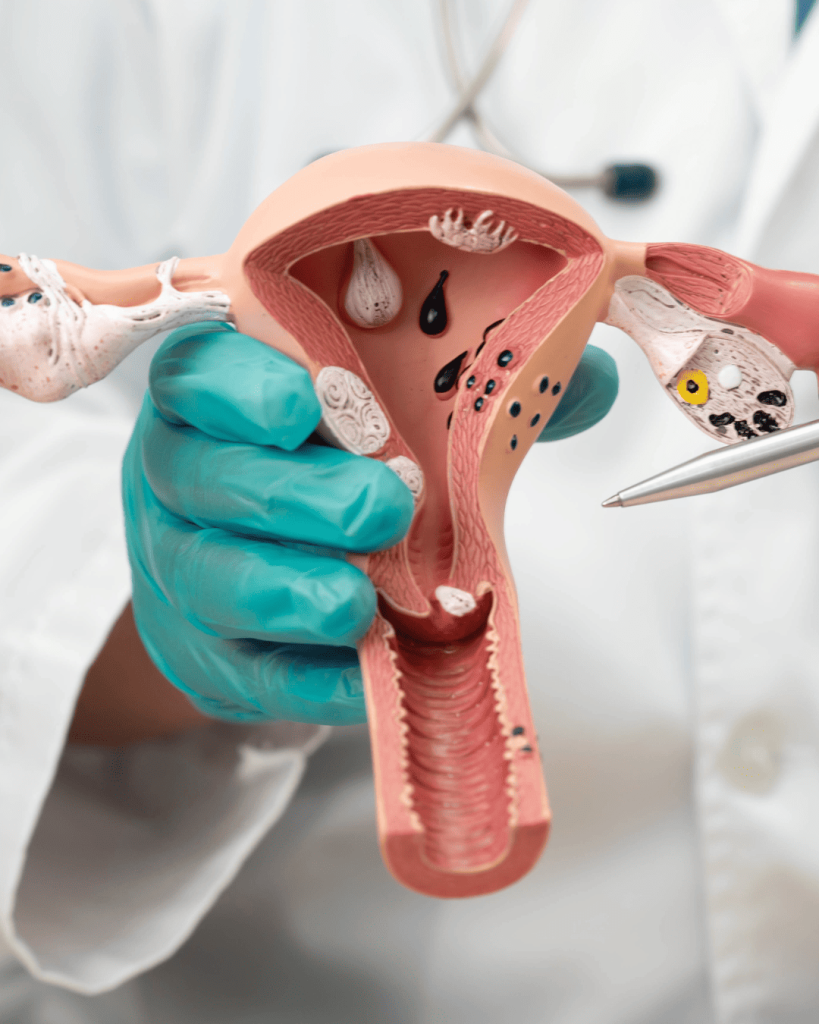

The endometrial immunology test is a diagnostic evaluation that checks for immune system activity in the uterine lining that could interfere with embryo implantation or lead to early pregnancy loss. Even when high-quality embryos are transferred during IVF, certain immune responses—like elevated natural killer (NK) cell activity—can prevent successful implantation.

At EPIA, this test is recommended for individuals with recurrent implantation failure, repeated miscarriages, or conditions like endometriosis. It helps us identify hidden inflammatory or immunological factors and allows for more precise cycle planning and immune-based treatments.

- Step 3: Laboratory Analysis - The sample is sent to a specialised lab to check for natural killer (NK) cell concentration, cytokine profiles, and signs of immune dysregulation.

It evaluates immune activity in the uterine lining, including levels of natural killer (NK) cells, cytokines, and other markers that may interfere with embryo implantation.